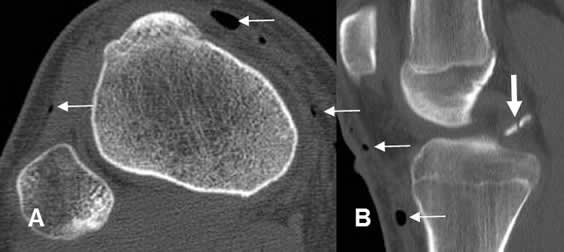

Fig 51. Avulsión del codo.

Desplazamiento inferior del núcleo de crecimiento, del epicóndilo medial.